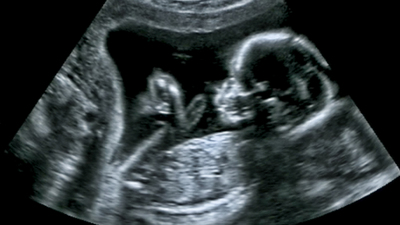

ABD´deki New York kentinde Mount Sinai Icahn Tıp Fakültesi'nde çevre ve üreme epidemiyolojisi uzmanı olan Dr. Shanna Swan, düşük sperm sayıların ve cinsel gelişimdeki değişikliklerin insan neslini tehlikeye atabileceğini açıkladı. Dr. Swan, "Count Down (Geriye Sayım)" adlı kitabında insanlığın doğurganlık kriziyle karşı karşıya kalacağını ifade etti. Swan, yaklaşan doğurganlık krizinin iklim kriziyle karşılaştırılabilir küresel bir tehdit oluşturduğu konusunda uyardı.

2017'de ortak yazarı olduğu bir araştırmanın ardından araştırmaya dayanarak hazırladığı kitabında, batıdaki sperm sayısının 1973 ile 2011 yılları arasında yüzde 59 oranında düştüğünü belirten Dr. Swan "Üreme olaylarının mevcut durumu, insan sağ kalımını tehdit etmeden daha uzun süre devam edemez" ifadelerini kullandı. Swan, mevcut tahminleri takiben medyan sperm sayısının 2045'te sıfıra ulaşacağını belirtti.

Count Down kitabının yazarı Swan ve yardımcı yazarı Stacey Colino; insanların çok fazla kimyasallara maruz kaldığını ve bu durumun doğurganlığı tehdit ederek insanların nesli tükenmekte olan bir tür haline gelebileceğini öne sürdü. Kitapta, 1964 ile 2018 arasında küresel doğurganlık oranı kadın başına 5,06 doğumdan 2,4'e düştüğü ifade edilirken dünya ülkelerinin yaklaşık yarısının doğurganlık oranları, nüfus yenileme düzeyi olan 2,1'in altında kaldığı belirtildi.